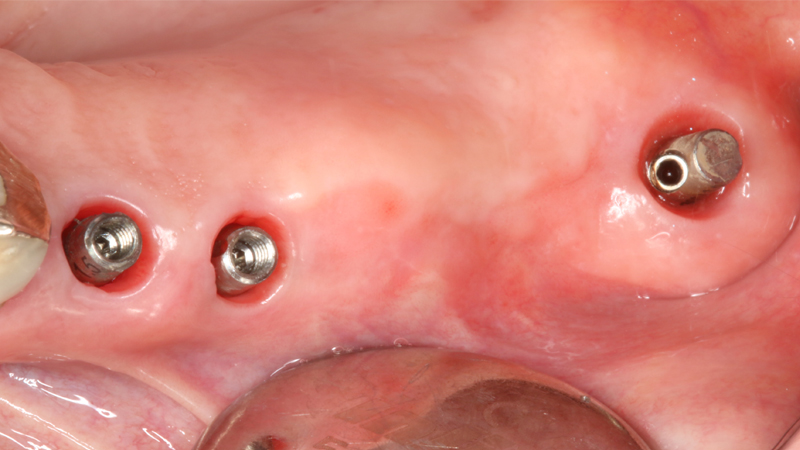

Sul 12 veniva eseguito un impianto post-estrattivo con carico immediato mediante moncone conometrico e provvisorio ricavato ribasando una cappetta provvisoria in peek e applicazione a frizione mediante conometria (Figs. 19, 20, 21, 22, 23).

Carico immediato su 12 con moncone conometrico dritto e cappetta provvisoria in peek ribasata in resina su provvisorio. Foto dopo l'intervento con esecuzione flapless e leggera plastica gengivale del Tuber applicazione di cappette di guarigione in peek. Guarigione dei tessuti dopo 3 mesi e impronta digitale definitiva per finalizzare il caso